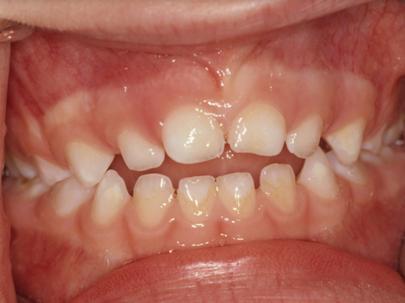

非营养性吮吸习惯可能与乳牙列和混合牙列的错牙合畸形患病率增加以及上前恒牙外伤的发生风险增加相关。可能会出现以下图片中的问题,包括前牙开牙合;后牙反牙合;深覆盖和上颌相对下颌过于前突的Ⅱ类错牙合。